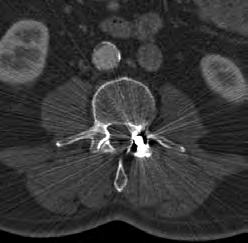

Który artefakt jest widoczny na skanie tomografii komputerowej?

A. Metaliczny.

B. Elektrostatyczny.

C. Utwardzonej wiązki.

D. Ruchowy.